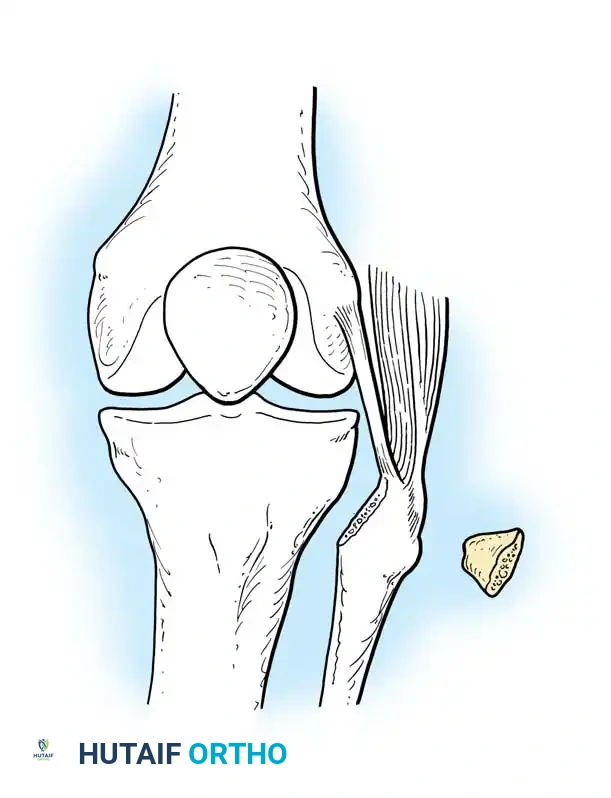

Surgical Atlas: Osteotomy and Realignment Biomechanics

The following radiographic and illustrative figures detail the preoperative planning, biomechanical axes, and intraoperative fixation strategies critical for successful osteotomies around the knee.

Preoperative templating is mandatory. The mechanical axis must be drawn from the center of the femoral head to the center of the ankle mortise. The degree of correction is calculated to ensure the new weight-bearing line passes through the targeted compartment.

Intraoperative fluoroscopy is utilized to confirm the osteotomy trajectory. Guide pins are placed parallel to the joint line, ensuring the hinge point remains intact to provide intrinsic stability to the osteotomy site.

Rigid internal fixation is achieved using anatomically contoured locking plates. In opening wedge osteotomies, the plate acts as a buttress to maintain the correction angle while the osteotomy heals.

Careful soft tissue management is required. In medial opening wedge HTO, the superficial medial collateral ligament (sMCL) must be partially released distally to allow the osteotomy to open without increasing medial compartment contact pressures.